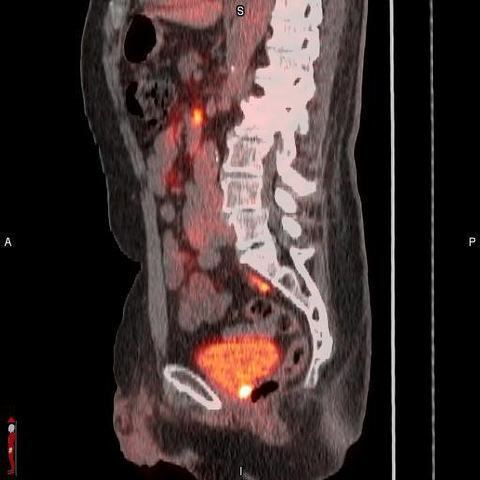

MONROE TOWNSHIP, N.J. & OXFORD, England--(BUSINESS WIRE)--Blue Earth Diagnostics, a Bracco company and recognized leader in the development and commercialization of innovative positron emission tomography (PET) radiopharmaceuticals, today announced results from a post-hoc analysis from the Phase 3 SPOTLIGHT trial (NCT04186845) that investigated the use of POSLUMA® (flotufolastat F 18) PET in suspected biochemical recurrence of prostate cancer. The analysis examined the detection rate (% positive PET scans) in a subset of patients with low-very low Prostate Specific Antigen (PSA) levels. POSLUMA® (flotufolastat F 18) injection (formerly referred to as 18F-rhPSMA-7.3) is indicated for positron emission tomography (PET) of prostate-specific membrane antigen (PSMA) positive lesions in men with prostate cancer with suspected metastasis who are candidates for initial definitive therapy or with suspected recurrence based on elevated serum prostate-specific antigen (PSA) level.

“Recurrent prostate cancer presents clinical challenges, and the ability to determine the extent and location of recurrent disease is necessary to inform physicians and their patients for appropriate clinical management,” said Ashesh B. Jani, MD, MSEE, FASTRO, Winship Cancer Institute of Emory University, Atlanta, Ga., on behalf of the SPOTLIGHT Study Group. “The SPOTLIGHT study investigated the diagnostic performance of POSLUMA PET imaging as a potential decision-making aid in assessing suspected biochemical recurrence of the disease, and demonstrated precision diagnostic performance, with an overall 83% (322/389) detection rate. This post-hoc analysis further examined POSLUMA performance in 188 men with low-very low PSA levels. Results showed that more than two-thirds of these men were found to have positive POSLUMA scans, with a quarter of them having extrapelvic lesions. POSLUMA PET may be a useful tool for treatment planning, particularly in patients with suspected early recurrence of disease who may be candidates for curative salvage therapy.”

“We are pleased to present these results to the radiation oncology community at ASTRO,” said David E. Gauden, D.Phil., Chief Executive Officer of Blue Earth Diagnostics. “POSLUMA has recently been added to nationally recognized clinical oncology guidelines for prostate cancer, alongside and for all the same categories as the other currently FDA-approved PSMA PET radiopharmaceuticals. Our new product represents a new class of high-affinity PSMA-targeted radiopharmaceuticals based on novel radiohybrid technology and provides physicians with high-quality information based on these good detection rates at low PSA levels, high-affinity PSMA binding and low urinary bladder activity. The product is labeled with the radioisotope fluorine-18 (18F) to leverage high image quality and to enable broad, readily available geographic access for patients via the manufacturing and distribution network of our commercial U.S. manufacturer and distributor, PETNET Solutions Inc, A Siemens Healthineers Company.”

- In total, 389 patients (median [range] PSA, 1.10 [0.03–135] ng/mL, 84 with intact prostate) had an evaluable flotufolastat F 18 scan. The overall DR was 83% (322/389) by majority read. Of the 389 patients with an evaluable flotufolastat F 18 scan, 188 had a baseline PSA <1 ng/mL and were eligible for the present analysis. Despite low patient numbers in some PSA categories, moderate to high DR were observed, with the patient-level DR shown to increase with increasing baseline PSA. Overall, 68% (128/188) of patients with a PSA <1 ng/mL and 64% (77/121) of patients with a PSA <0.5 ng/mL had a positive flotufolastat F 18 scan by majority read. Regional DRs were broadly consistent across all PSA categories. Extrapelvic lesions were observed in 21% (25/121) of patients with a PSA <0.5 ng/mL, increasing to 39% (26/67) in patients with a PSA of ≥0.5 to 1 ng/mL.